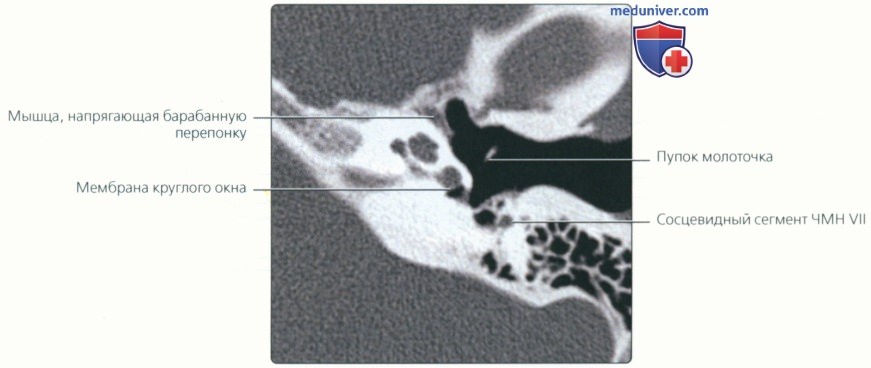

КТ анатомия сосцевидного отростка: особенности и показания